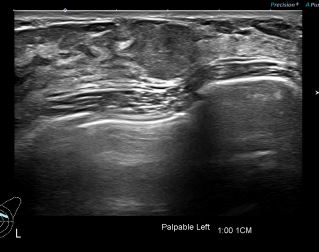

상기환자 만져지는 멍울 및 통증있어 내원하신 30대 여성분으로

좌측유방 혹 총조직검사 시행해 유방암 진단되었습니다.